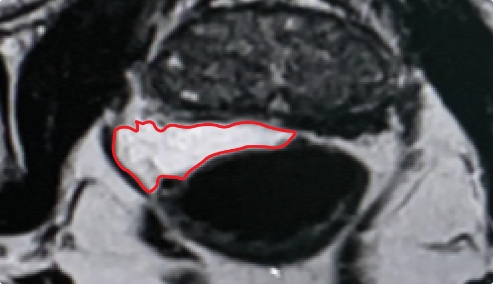

PEG HYDROGEL

Lack of control over placement of the implant can result uneven and inconsistent coverage.

Implant Symmetry RESULTS7

49%

Pivotal Trial Patients; % of implants centered on prostate midline